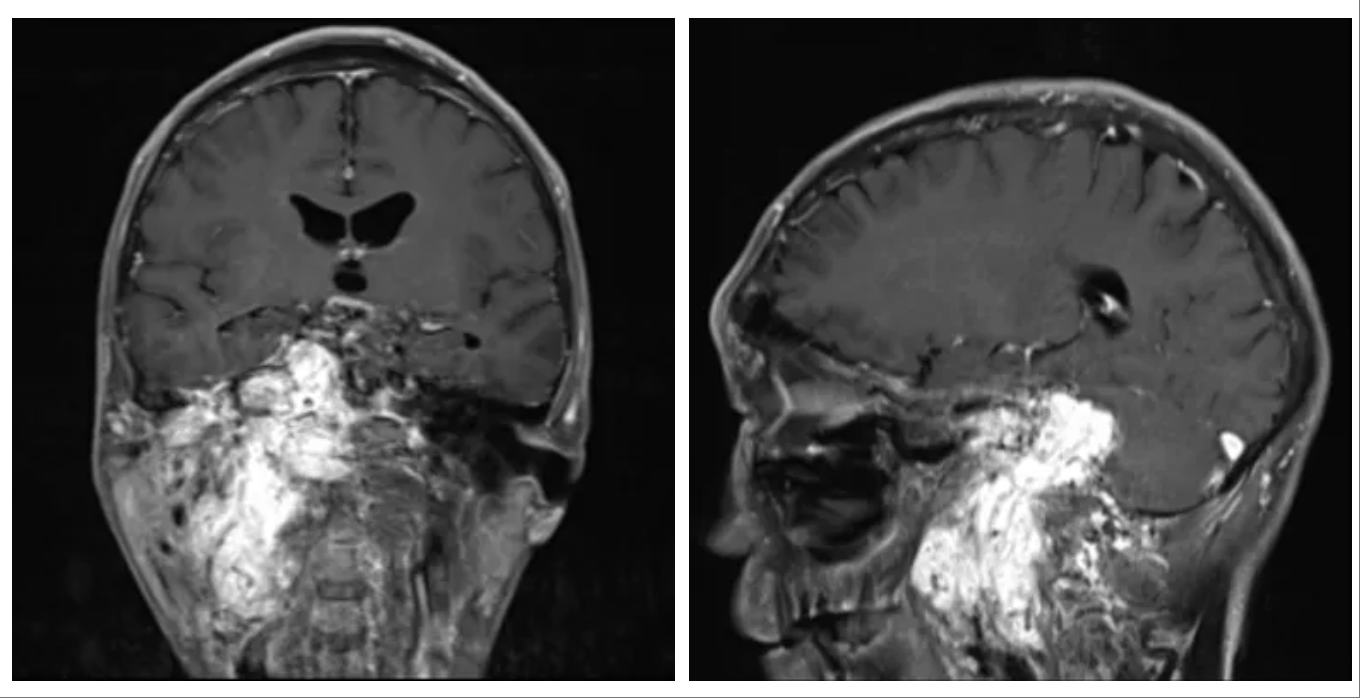

今年6月,扎西在外院检查后发现,其颅底颈静脉孔区存在巨大颅内外沟通肿瘤,这个肿瘤正是导致他十多年来所有症状的根源。

巨大颅内外沟通肿瘤暗藏杀机

处理颈静脉孔巨大颅内外沟通肿瘤,远不止是“棘手”二字可以概括,它是神经外科领域公认的顶尖挑战之一。扎西此前多方辗转求医,得到的多半是无奈地摇头。

上海冬雷脑科医院脑血管专家盖延廷主任介绍:“颈静脉孔是颅底的一个骨性孔道,像一条至关重要的‘电缆管道’,里面有负责大脑血液回流的颈内静脉、负责大脑供血的颈内动脉等关键‘电缆’通过。

此例颈静脉孔巨大颅内外沟通肿瘤具有三重高危特性

一是贯穿颅内外,经颈静脉孔同时侵犯颅内和颈部,手术需要同时打开颅腔和颈部,解剖结构更复杂;

二是肿瘤血供异常丰富,10多根血管深入瘤体缠结,手术中将出血凶猛;

三是肿瘤区域与颈静脉孔中的‘电缆’、脑干紧密粘连,稍有不慎将导致神经受损,甚至呼吸心跳骤停。”